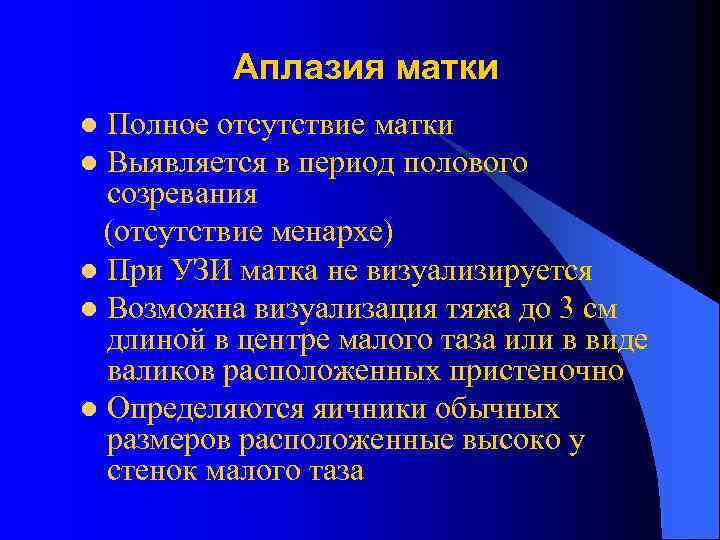

Аплазия матки Полное отсутствие матки l Выявляется в период полового созревания (отсутствие менархе) l При УЗИ матка не визуализируется l Возможна визуализация тяжа до 3 см длиной в центре малого таза или в виде валиков расположенных пристеночно l Определяются яичники обычных размеров расположенные высоко у стенок малого таза l